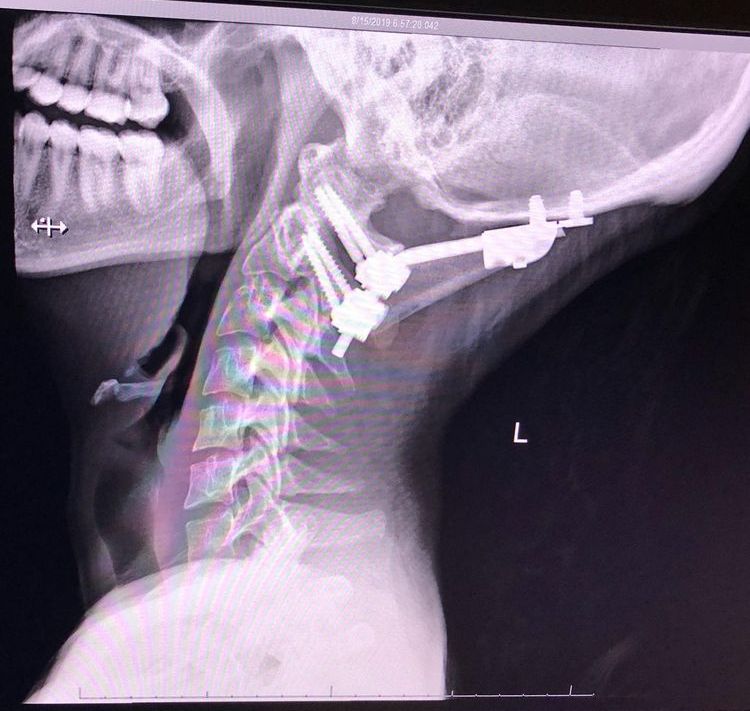

Медицинское приспособление для поддержания шеи в правильном положении при заболевании соединительной ткани, которое называется синдром Элерса-Данлоса

«Связки, удерживающие мою голову, больше не хотели выполнять свою работу, и моя шея ослабла».